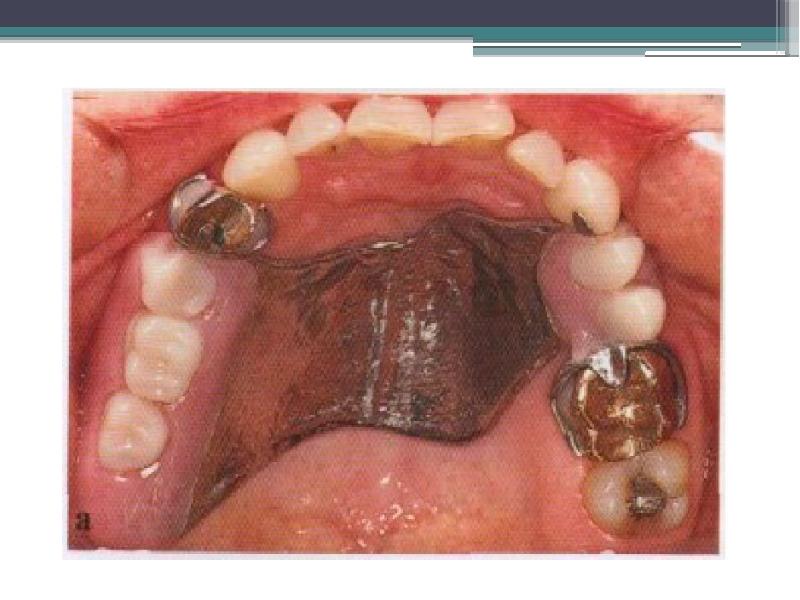

- 5. Девочка с дефектом твёрдого нёба, общей площадью до 10 см2